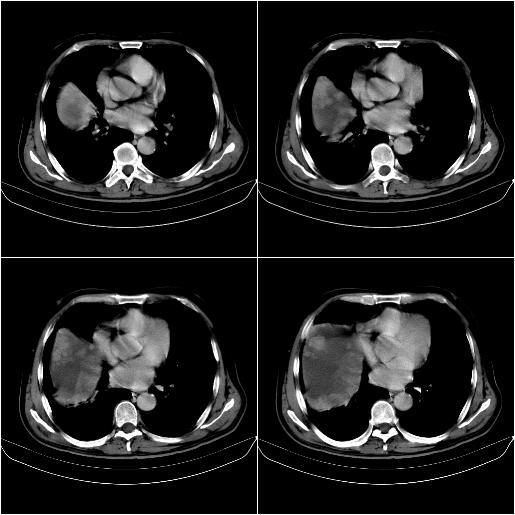

标题: CT21651:M,67Y,肝癌9月,介入术后3月。

m,67y,肝癌9月,介入术后3月。现腹胀、纳差、腹泻。

门静脉有很大的瘤栓,膈肌及膜膜有转移,不用再做了.

情况不好,门静脉癌栓、腹膜转移。

1)肝癌介入治疗术后碘油沉积不良。2)门静脉瘤栓形成,腹膜广泛性转移。3)肝硬化,脾大,腹水。4)慢性胆囊炎。